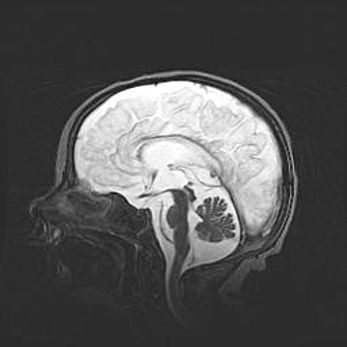

Мальформация Денди-Уокера. Киста задней черепной ямки.

Агенезия мозолистого тела.

Возраст: 2,5 месяца

Вес: 2420 г

Пол: женский

Окружность головы: 37 см

Срок гестации: 32 недели

Мальформация Денди—Уокера — редкий вид патологии ЦНС, представляющий собой врожденный порок развития каудального отдела ствола и червя мозжечка, ведущий к неполному раскрытию срединной (Мажанди) и латеральных (Лушка) апертур IV желудочка мозга. Для этогно синдрома характерна триада симптомов: гипотрофия червя мозжечка и/или полушарий мозжечка, кисты задней черепной ямки, гидроцефалия различной степени. В 70% случаев порок сочетается и с другими аномалиями головного мозга, в частности с агенезией мозолистого тела.